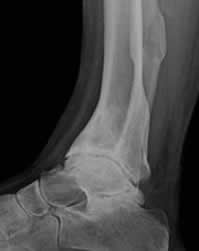

Fig 138. Artropatía neuropática. Patrón hipertrófico.

Rx lateral. Disminución del espacio tibioastragalino, con esclerosis y formación de osteofitos anteriores. Fractura consolidada de la tibia, como desencadenante.